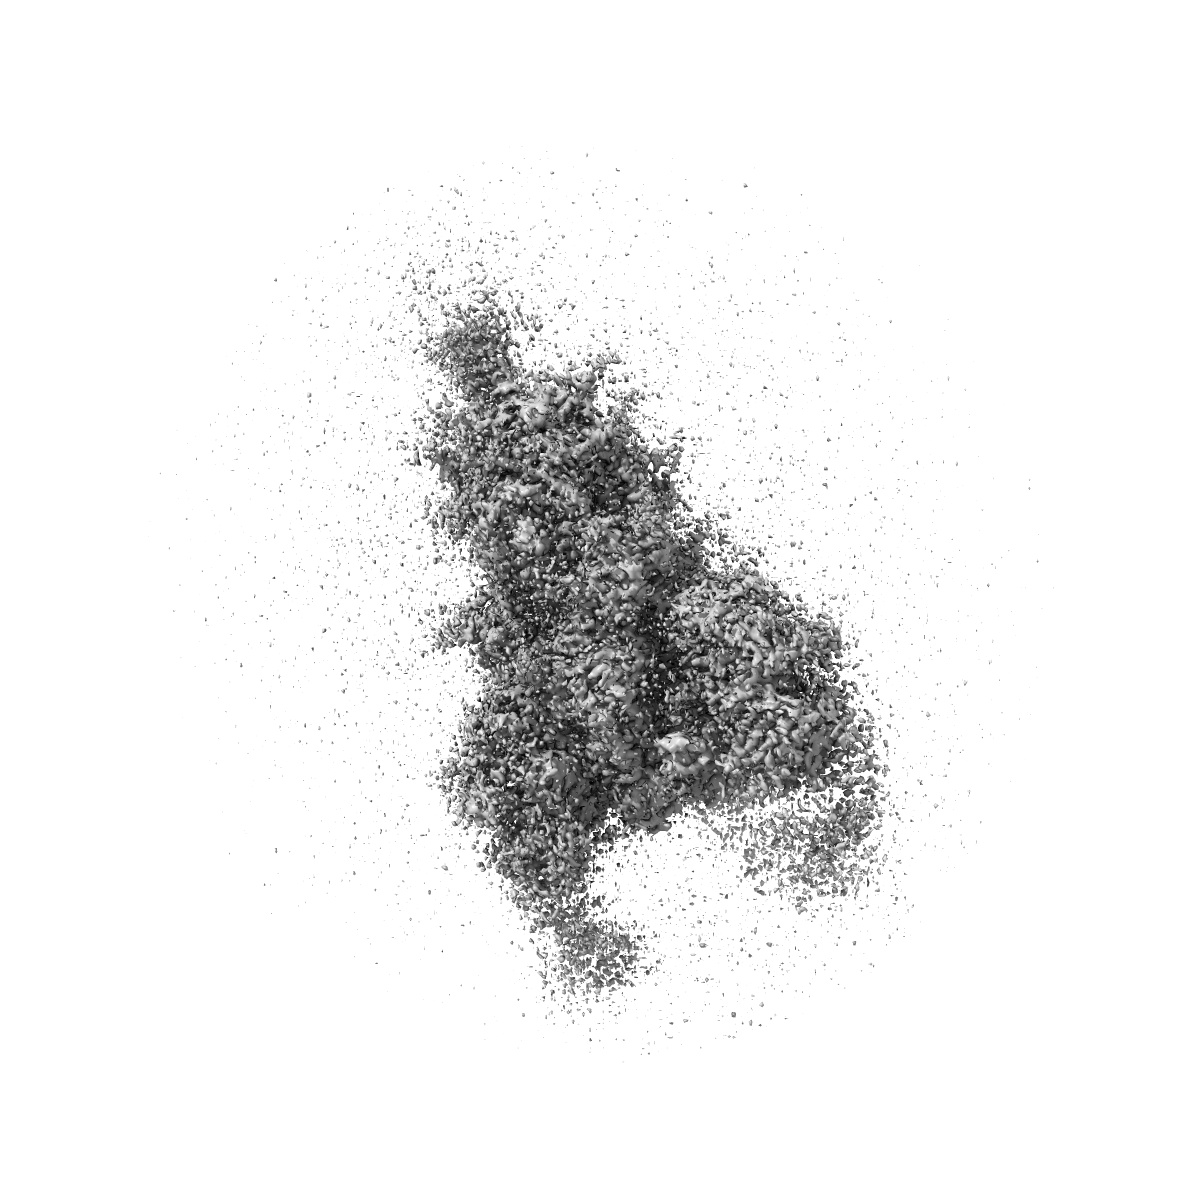

S protein of SARS-CoV-2 in complex with 3711

Single-particle2.8 Å

Sample: S protein of SARS-CoV-2 in complex with 3711

Defining the features and structure of neutralizing antibody targeting the silent face of the SARS-CoV-2 spike N-terminal domain.